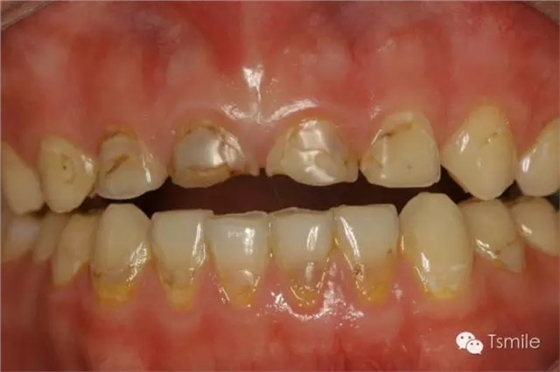

對(duì)牙齒酸蝕脫礦的酸來源于患者身體以外,包括飲料、食物、水果、藥物、工作環(huán)境等。碳酸類飲料如可樂,其PH值約為2.7;果汁中檸檬汁的PH值約為1.8-2.4。酸性的飲料、水果、食物等長(zhǎng)時(shí)間、高頻度地接觸牙齒表面,導(dǎo)致牙齒表面硬組織酸蝕脫礦,造成牙齒表面硬組織的重度缺損。

圖3:酸性飲料導(dǎo)致的牙列重度磨耗(酸蝕癥) (2)內(nèi)源性酸蝕 對(duì)牙齒酸蝕脫礦的酸來源于患者身體內(nèi)部的胃液。胃液的PH值約為1.6-1.9,酸性很強(qiáng),對(duì)牙齒硬組織具有很強(qiáng)的酸蝕脫礦能力。但胃液怎么會(huì)進(jìn)入口腔內(nèi)對(duì)牙齒造成酸蝕脫礦呢?引起胃液導(dǎo)致的內(nèi)源性酸蝕癥的疾病主要有以下兩種: